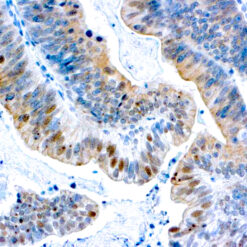

Solitary fibrous tumor (SFT) is a fibroblastic neoplasm of variable biologic potential that can arise at a wide range of anatomic sites. Almost all cases of (98%) including conventional, cellular, atypical, and malignant variants showed nuclear expression of STAT6. Staining for STAT6 was usually diffuse: 68% of cases showed reactivity for STAT6 in 75% of tumor cells. Further, the intensity of staining was strong in 67% of cases, moderate in 25%, and weak in only 7%. The heterogeneity of staining, both in terms of extent and intensity, which may be because of uneven tissue fixation or loss of antigenicity in older cases for which the unstained slides were stored for extended periods of time. All other tumor types examined were negative for STAT6, except for three dedifferentiated liposarcomas and one deep fibrous histiocytoma, which showed weak staining. STAT6 is therefore a highly sensitive and almost perfectly specific immunohistochemical marker for SFT, and can be helpful to distinguish this tumor type from histologic mimics.